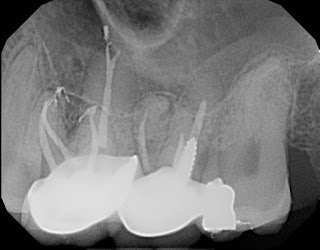

One of the biggest claims made regarding the GentleWave technique is “improved removal of organic matter” and creating a “higher standard of clean”. Evidence provided for this claim are usually images of more complex anatomy picked up when the tooth is obturated. The advocates call this “the thrill of the fill”.

However, the idea of cleaning and filling lateral canals and isthmuses is not unique to GentleWave. In our practice we have used both ultrasonic and sonic activation of irrigating solutions which has provided 3D cleaning and shaping of complex canal anatomy.

I have included several radiographic that demonstrate the “Thrill of the Fill” routinely seen at SSE using sonic activation of irrigating solutions. After our hands on demonstration with the GentleWave, I began putting aside radiographs after using sonic activation and found that the fill results were equally impressive.